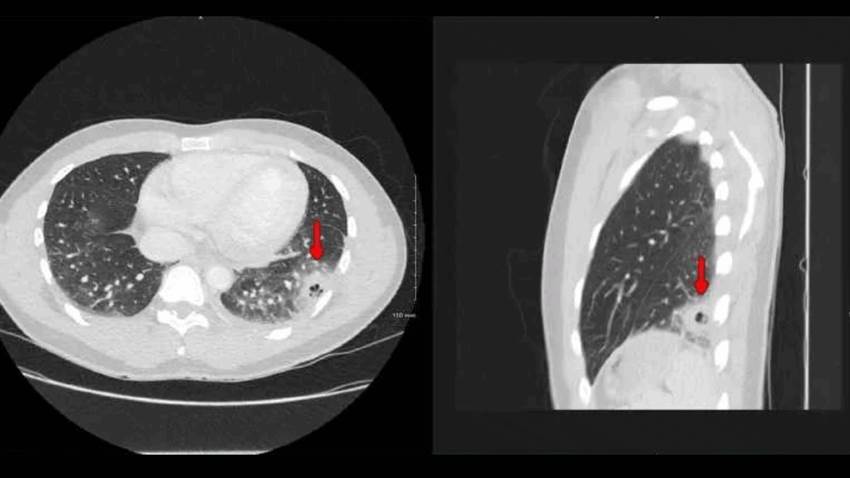

Paciente con COVID-19 desarrolla enfermedad pulmonar cavitaria como complicación a largo plazo del virus

En medio de la alerta salubrista en Puerto Rico ante el registro de complicaciones a largo plazo que ha provocado el COVID19 en pacientes que se han r...